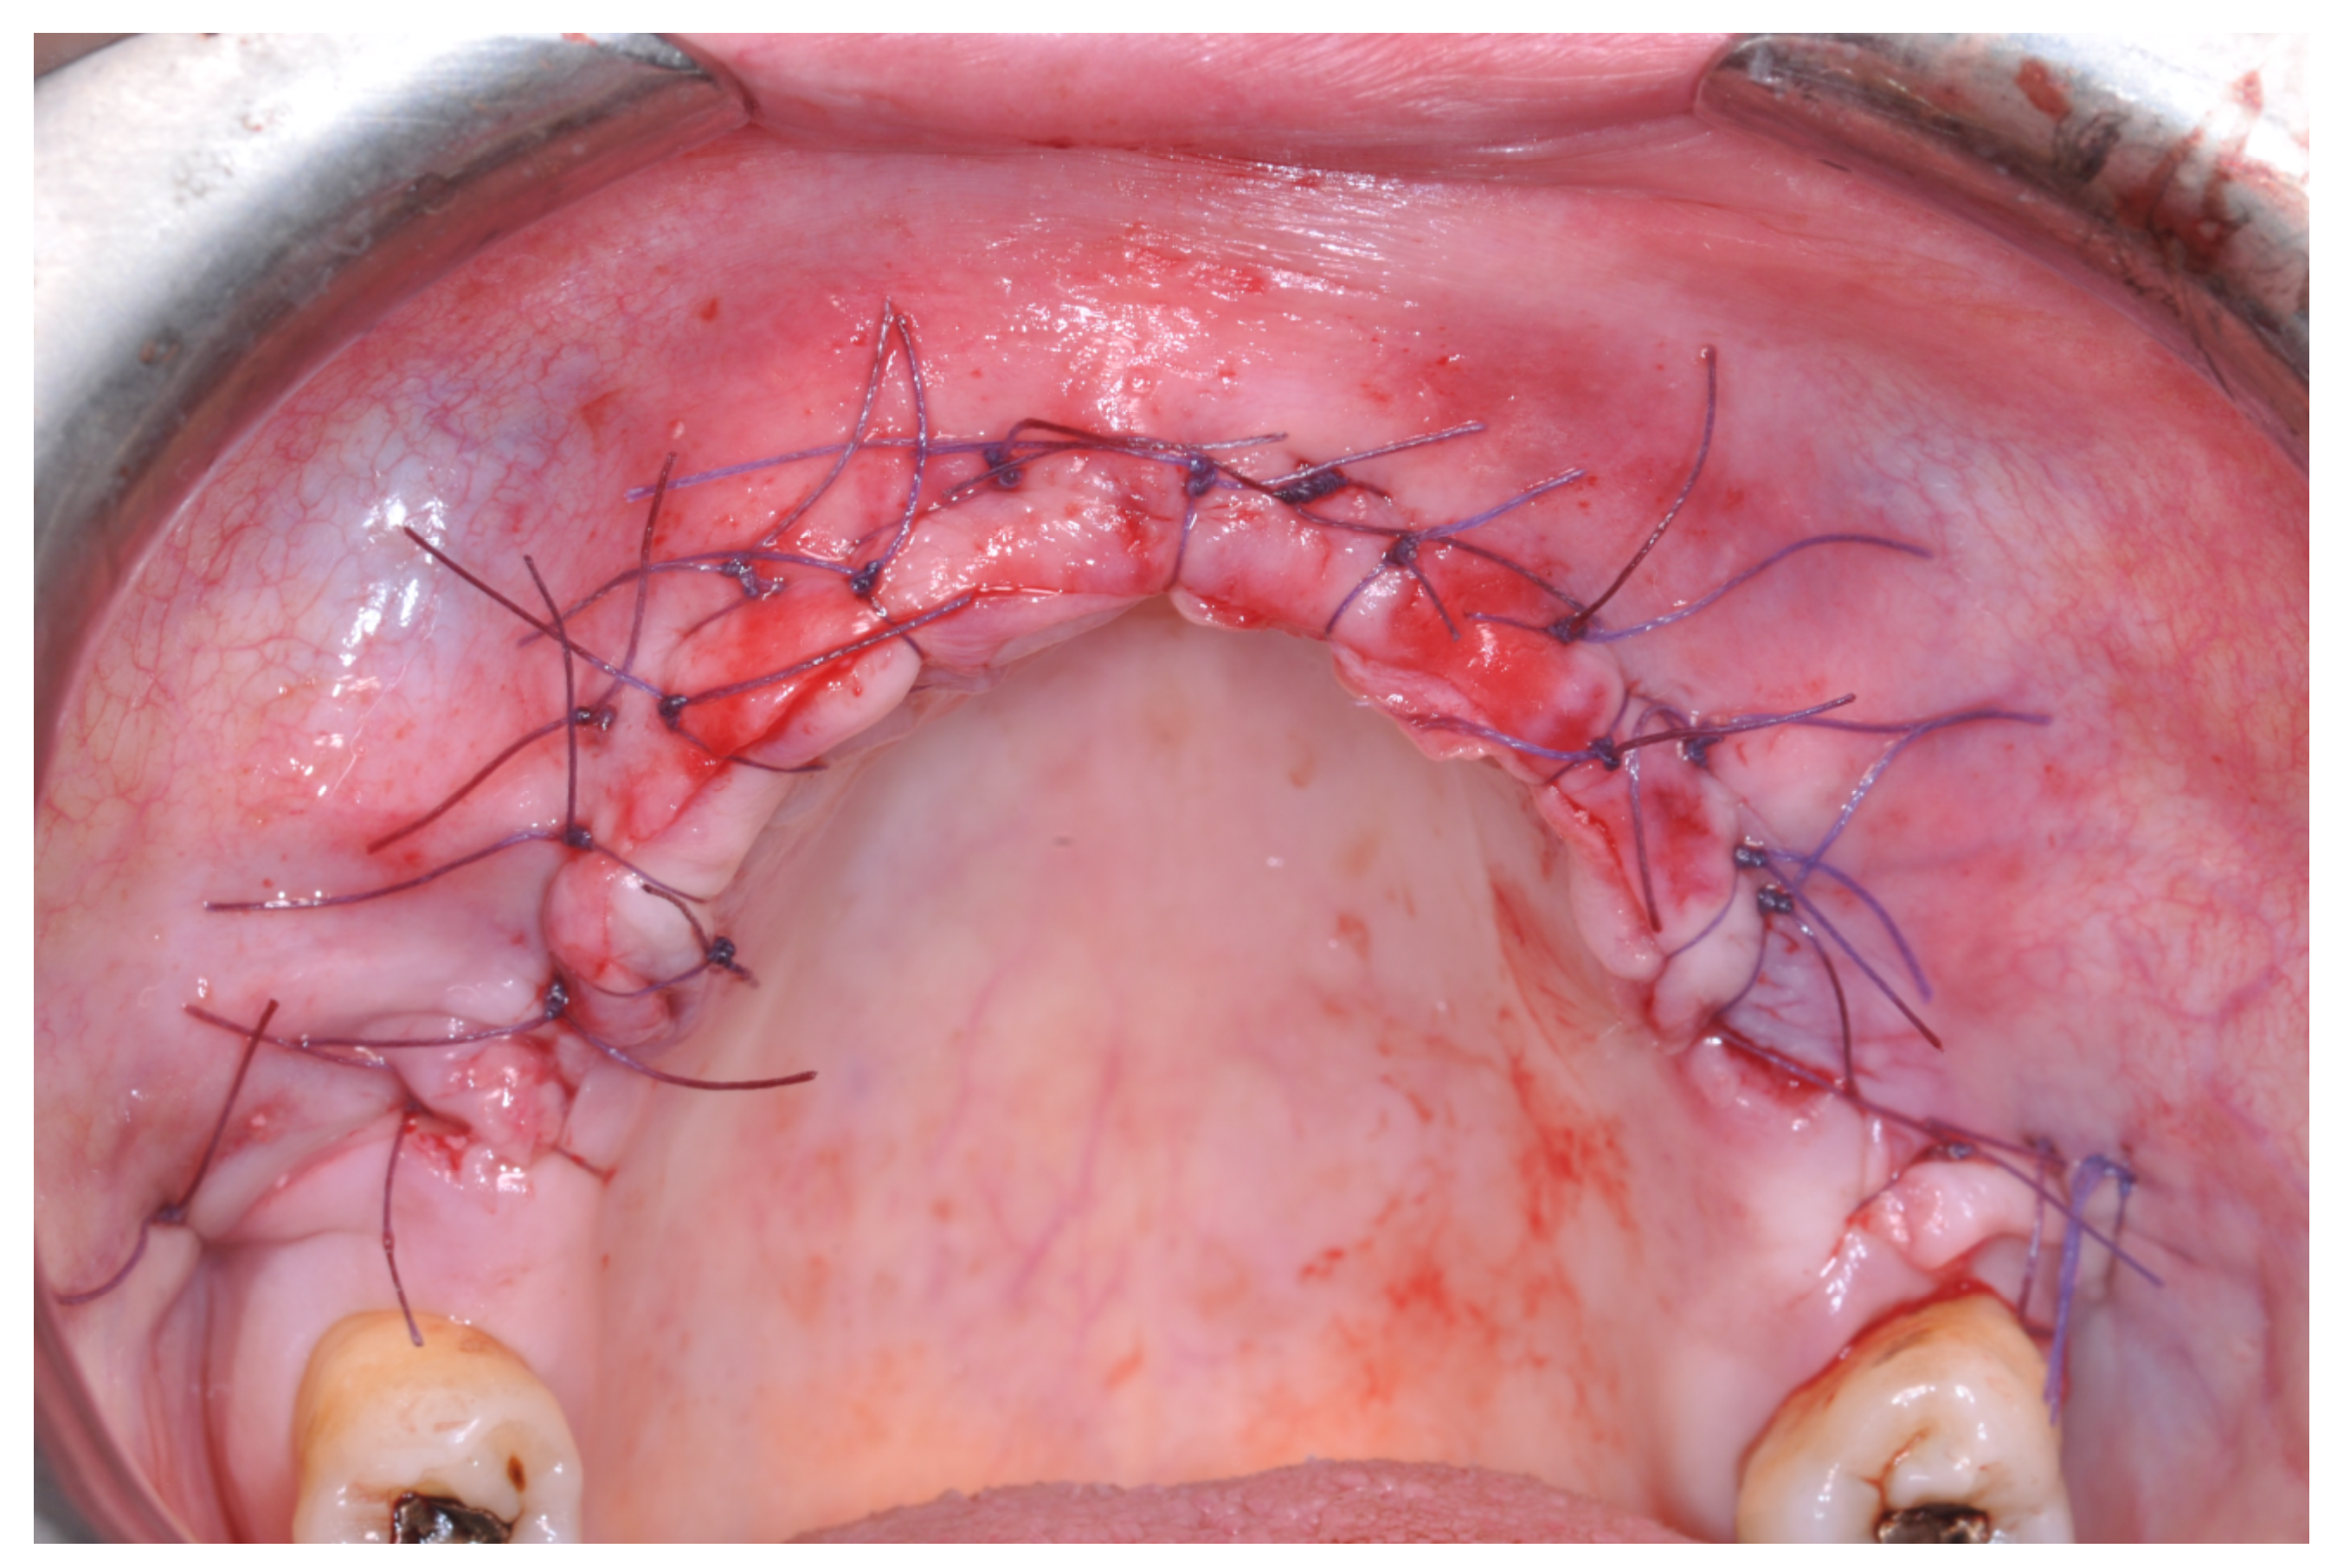

At this point, a non-resorbable high-density PTFE barrier (Cytoplast TXT-200, Osteogenics Biomedical, Lubbock, TX, USA) was designed on the basis of the bone defect shape and was distally blocked on the bone by two titanium pins (Kalos, Nike, Orbetello, Italy). A mixture of 50% autogenous bone harvested from the mandibular ramus with the use of a scraper and 50% inorganic bovine bone (Bio-Oss, Geistlich, Wolhusen, Switzerland) was placed in the recipient site and the membrane was pulled and blocked on the bone with two mesial pins. With this particular, and innovative, non-resorbable membrane management, the graft was compressed and fixed on the recipient bed (Figure 9, Figure 10 and Figure 11). The occlusal portion of the graft was then covered with a layer of a collagen resorbable barrier (Bio-Gide, Geistlich) (Figure 12) and peri-osteal incisions were performed to make the flap passive.

Resorbable sutures (Vicryl 6-0 SH1 needle of 17 mm 1/2c; Ethicon, New Brunswick, NJ, USA) were placed, alternating between single sutures and horizontal mattrass sutures (Figure 13).

Figure 13. After suturing.

Patients rinsed with a chlorhexidine mouthwash (0.2%) for 1 min immediately prior to the intervention. Local anesthesia were administered using mepivacaine with adrenaline at ratios of 1:100,000 or 1:50,000. Crestal incisions were made with releasing incisions far away from the future membrane positioning and full thickness flaps were elevated. After the meticulous removal of all residual soft tissues in the regenerating site, copious bleeding was induced using a bone scraper (Safescraper Curve TWIST, META, Reggio Emilia, Italy) (Figure 1). A prosthetically guided implant placement was performed following the instructions of manufacturer (Thommen Medical, Grenchen, Switzerland). Only 1 patient had implants placed 9 months after bone augmentation because the initial bone thickness did not permit the primary stabilization of the implant fixtures (Figure 2, Figure 3, Figure 4, Figure 5, Figure 6, Figure 7 and Figure 8).